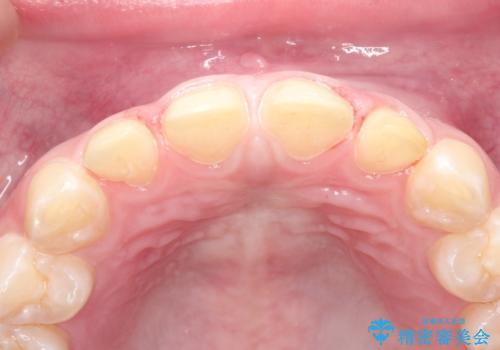

生まれつき歯の色が白濁しているところや、黄色くなっているところがあり、セラミッククラウンに審美的改善を行うこととしました。

ご自身の歯を削る必要がありましたが、セラミッククラウンを装着することで、審美的改善ができました。